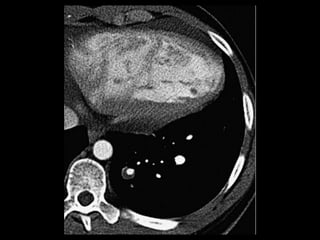

Sequestro intralobar com infecções recorrentes

Sequestro pulmonar Definição:segmento de tecido pulmonar que é separado da árvore brônquica e recebe seu suprimento sanguíneo de uma artéria sistêmica; Dois tipos: intralobar e extralobar; A maioria dos sequestros são tipo intralobar; O suprimento vascular em 80-90% dos casos provêm da artéria aorta descendente; Complicações: hemoptise e BCP repetição; Diagnóstico: identificação do vaso anômalo.

Sequestro intralobar cominfecções recorrentes